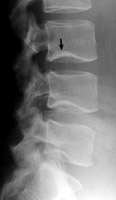

Diagnosis:Normal spine Discussion:Frontal and lateral radiograph of the lumbar spine with curvature of the inferior endplate of the 4th and 5th lumbar vertebrae, which mimics the curvature of Cupid's bow aimed cephalad. The unusual, non-flat surface of the inferior endplate is a normal variant, and need not be misinterpreted as inherent osseous abnormality or adjacent pathological process. References: